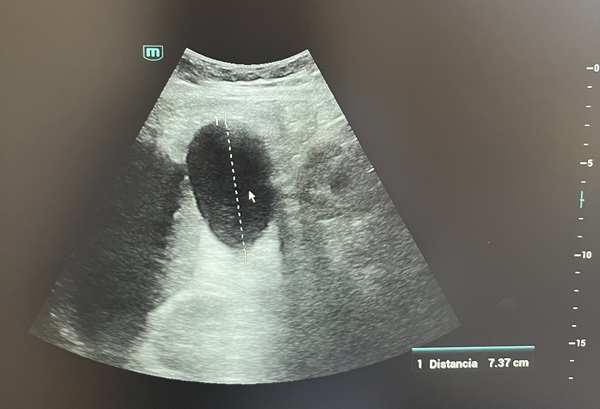

Descripción de los hallazgos ecográficos y las imágenes más relevantes para la resolución del caso

Vesícula biliar ligeramente distendida de 8,5 x 5 cm sin presencia de colelitiasis en su interior; impresionando dilatación de vía biliar intra y extrahepática.